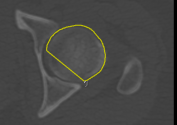

Adds a new path in Snap mode to the current group of paths. You use the Snap tool to create a path by simply dragging inside a feature on a 2D view. The contour line will automatically snap to the gradient that defines the edges of the targeted feature. Do the following to draw a path in Snap mode: